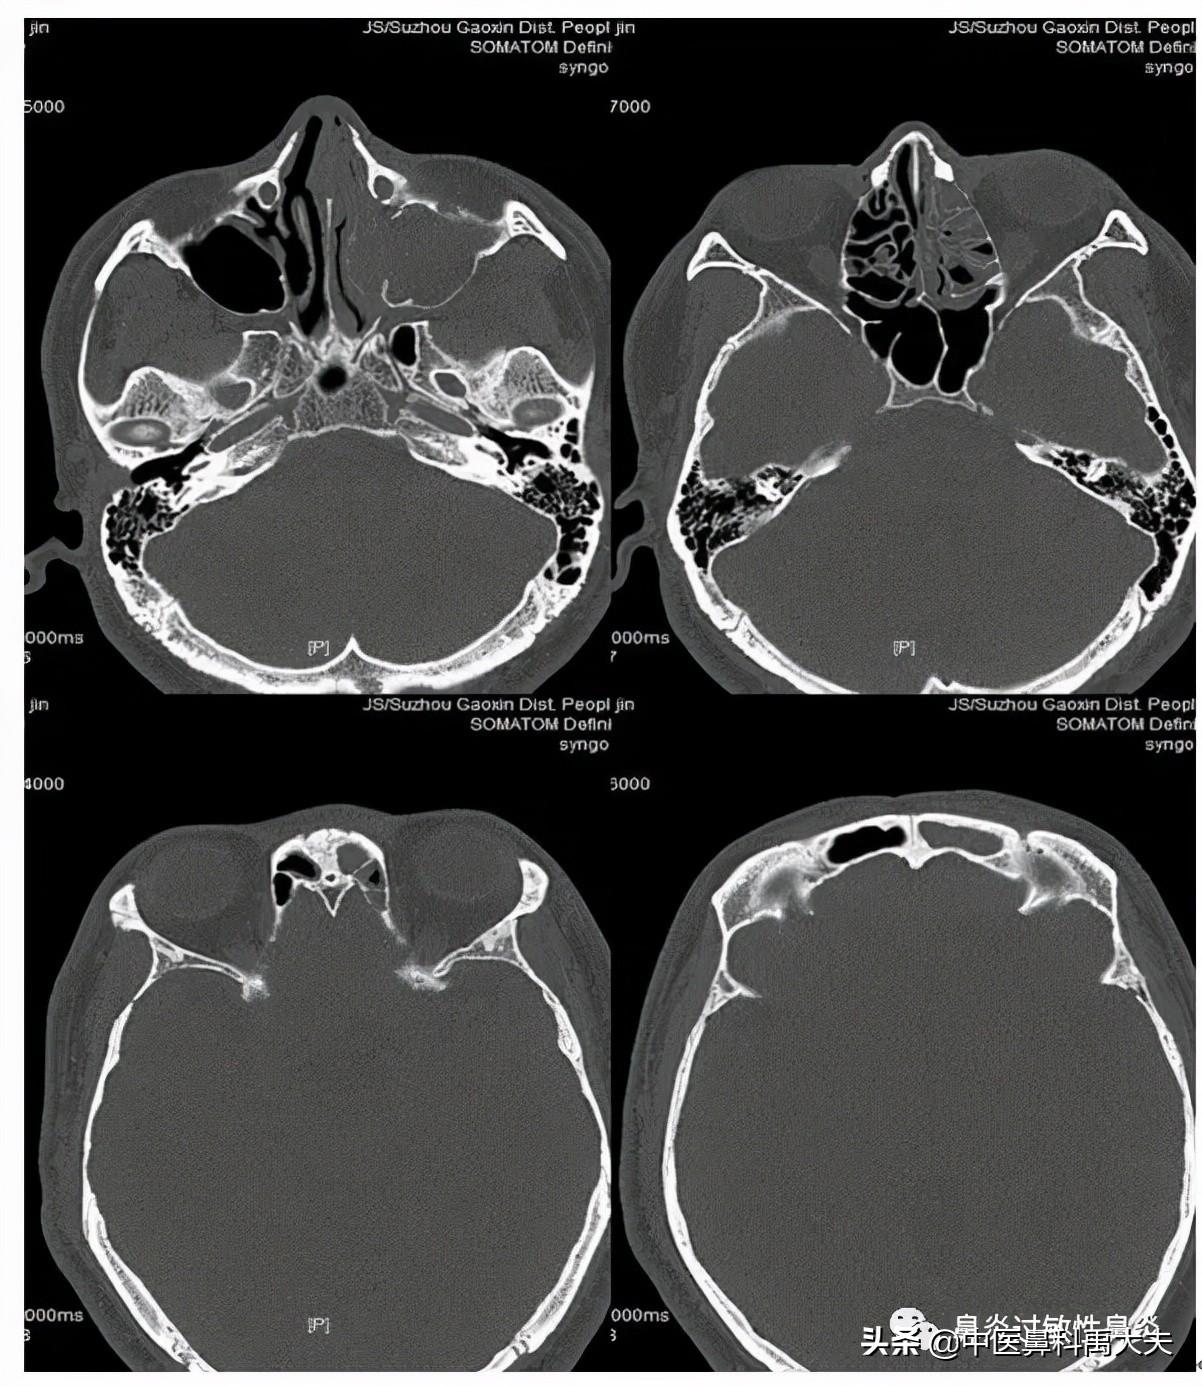

鼻窦炎就是指发生在窦腔黏膜的一种炎症性疾病,根据发病时间12周为界限,分为急性鼻窦炎和慢性鼻窦炎;但是现在的鼻窦炎大部分合并有慢性鼻炎,所以现在统称鼻鼻窦炎。

其次,我们还要知道可能引起窦口堵塞的原因,不只是鼻甲问题,如过敏性鼻炎的问题、鼻息肉的问题、真菌的问题等等,这些是我们常见的,所以治疗的时候,不但要处理鼻窦窦口的通畅引流问题,还要处理引起堵塞窦口的原因问题。